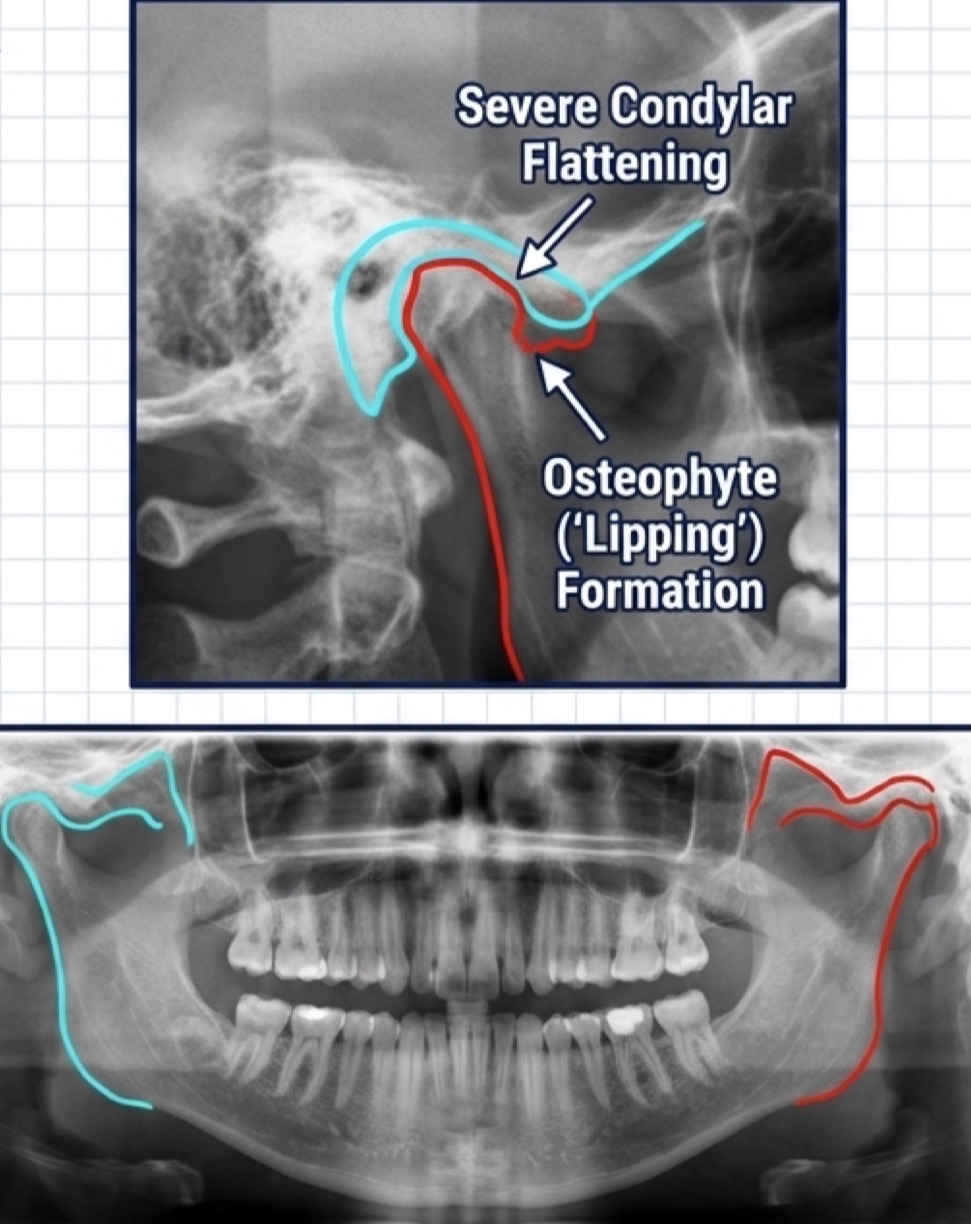

What is osteoarthritis- degenerative arthropathy- define, etiology, clinical symptoms, x ray, management?

Severely flat condyle, osteophyte (lipping) formation and cortical erosion